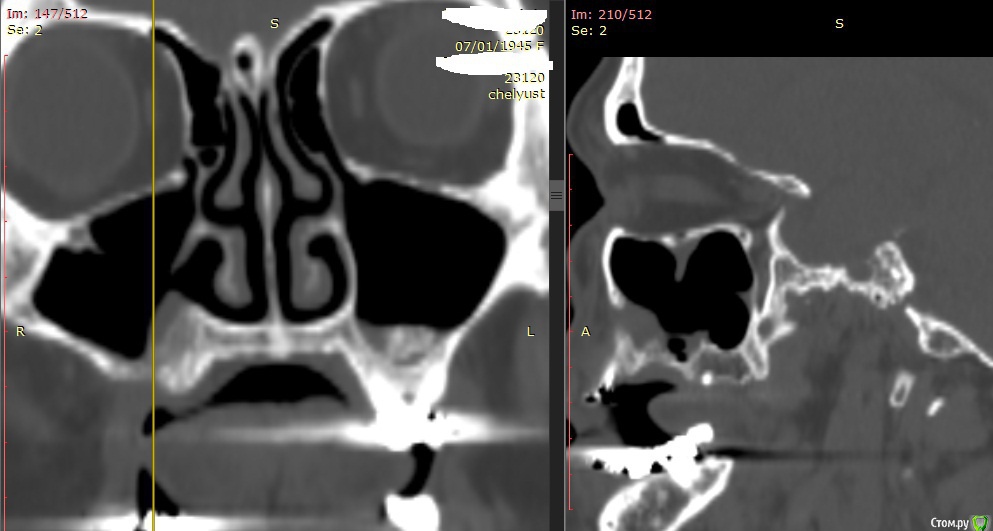

Alexey Doc Опубликовано 29 апреля, 2015 Поделиться Опубликовано 29 апреля, 2015 В клинику с целью протезирования обратилась пациентка 70 лет.Ортопед направил на консультацию. В анамнезе: со слов больной год назад удален зуб 1.6 после чего сформировался оро-антральный свищ. В январе 2015 года выполнена правосторонняя радикальная гайморотомия с удалением 1.5, 1.7 зубов. Сопутствующая патология в стадии компенсации.На сегоднещний день жалоб кроме отсутствия зубов нет.В полости рта : верхний свод преддверия справа плавно перетекает в небо мощным тяжем подвижной слизистой шириной примерно 15-17 мм . Альвеолярный отросток отсутствует. Какой\ие минимально инвазивные( учитывая возраст пациентки) способы аугментации вы бы применили у этой больной для последующего протезирования с опорой на имплантатах? Буду рад любому мнению и рац.предложению.Ниже свежие срезы КТ. Ссылка на комментарий

zzkz Опубликовано 29 апреля, 2015 Поделиться Опубликовано 29 апреля, 2015 Фото бы во рту еще.Не вижу естественного соустья. Если нет, опять к лору. То что искусственно сделали работать в должной мере не будет, нарушение дренажа приведет к проблемам. Мерцательный эпителий(кажется так называется) работает от природы в сторону естественного соустья.Еще есть гипертрофия слизистой.А так если слизистая пазухи и слизистая полости рта "одно целое" аккуратно сепарировать и мембрану с тит.усилением. Мобилизовать извините дохера надо. Потом слизистую щеки на место возвращать. Ссылка на комментарий

АнтонТЛТ Опубликовано 29 апреля, 2015 Поделиться Опубликовано 29 апреля, 2015 Фото бы во рту еще.Не вижу естественного соустья.на первом срезе 1 Ссылка на комментарий

Alexey Doc Опубликовано 30 апреля, 2015 Автор Поделиться Опубликовано 30 апреля, 2015 ткните пальцем не вижу что то)Хорошо проходимая решетчатая воронка Ссылка на комментарий